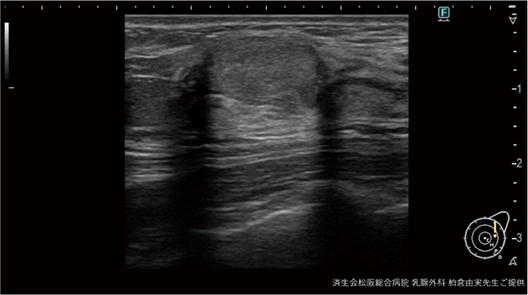

DeepInsightは電気ノイズだけを除去するので、後方エコー増強、外側陰影といった重要なアーチファクトはしっかりと残る(図1)。

図1:粘液癌